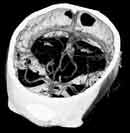

Плавающее фокальное пятно позволяет получить изображения с высоким разрешением даже при субсекундном сканировании. Более того, Volume Zoom обеспечивает режим субмиллиметрового сканирования, и позволяет получить изображения с высоким разрешением (30 пар линий/см).

Volume Zoom сделал существующие процедуры более быстрыми, более точными и более экономичными. Увеличивая пропускную способность в восемь раз, Volume Zoom предоставляет полностью новый спектр клинических приложений, которые изменили клиническую роль КТ.

Volume Zoom не только сокращает время обследования. Весь диагностический процесс разработан таким образом, чтобы увеличить производительность и интегрировать 3-мерную обработку в обычный диагностический процесс: быстрое сканирование, оптимальная обработка данных, простое управление консолью, качественные изображения, которые упрощают диагностику. Время экономится на каждом этапе процесса.